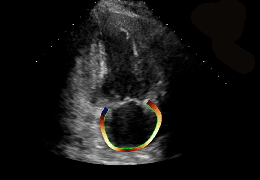

ART-Plan™ Artificial Intelligence Contouring